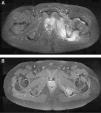

El segundo caso fue un varón de 14 años sin antecedentes de interés, que en el mes de julio consultó por cojera de 3 semanas de evolución, con antecedente de caída jugando al fútbol. En la exploración física se objetivaron fiebre, actitud antiálgica de cadera izquierda y flexo de rodilla izquierda con dolor a la movilización. En la analítica sanguínea se apreció: leucocitosis (12.100mg/dl) con desviación izquierda (83% de neutrófilos), VSG de 79mm/h y PCR de 4,80mg/dl. En la radiografía de fémur izquierdo se objetivó un aumento de partes blandas a nivel de vasto interno del cuadríceps. La RMN (fig. 2) demostró la presencia de un absceso del MOI que se extendía a través del agujero obturador por el muslo hasta la rodilla (fig. 2). El tratamiento consistió en el drenaje quirúrgico urgente del absceso y la administración posterior de antibioterapia por vía intravenosa (cloxacilina).